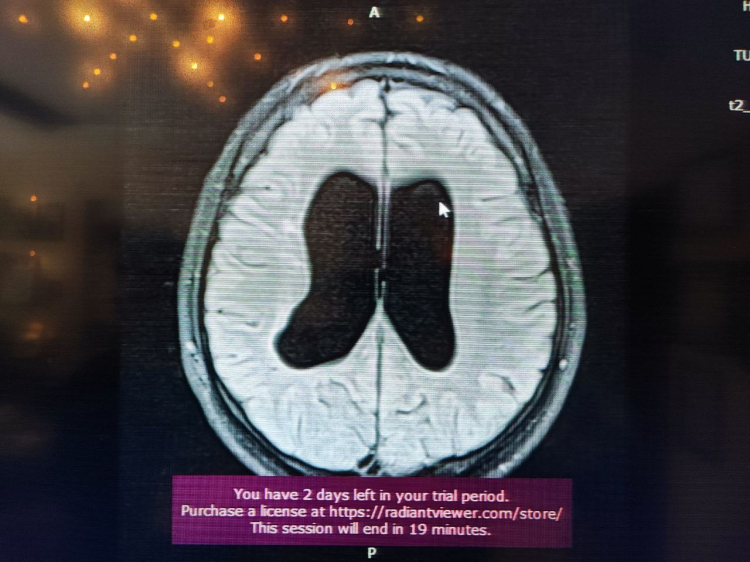

Süreçle ilgili bilgi veren Beyin, Sinir ve Omurilik Cerrahisi Uzmanı Prof. Dr. Orhan Şen, "17 yıl önce, 10 günlük bebekken annesi ve dedesi tarafından bana getirildi. Doğar doğmaz doktorlar ameliyat önermişler. Hidrosefali nedeniyle beyinde su toplanması var, bu nedenle acil ameliyat etmemiz gerekiyor yoksa ölür demişler. Gaziantep ve Adana'da farklı yerlere götürmüşler. Genel olarak hep ameliyat demişler. Ben muayenesini yaptım ve bıngıldak denilen yere baktığımda normal bombelikteydi. Anneye sordum, normal dururken kusma var mı? diye. ‘Hayır, yemek yerken kusma oluyor' dedi. Muayeneye devam ettiğimde çocuğun klinik tablosu, nörolojik muayenesi ve filmi birbiriyle uyumlu değildi. Bunun üzerine acil ameliyat gerekmiyor, izleyelim. dedim. Bıngıldakta bombe olursa ve arka arkaya kusma olursa o zaman ameliyatını yaparız dedim. Normalde ilk anne karnındayken gelişen süreçte olan bir olay. Radyolojik olarak çocuğun doğar doğmaz bu bulguyu görmemiz, hepsinin aktif hidrosefali olduğu anlamına gelmiyor. Bazen yeni doğanlarda olan ufak kanamalardan kaynaklanabiliyor" dedi.

Sözlerini sürdüren Prof.Dr. Şen "Bizim çocuğumuzda, anne karnında yaşanan bir süreç olduğu için beyine ekstra bir baskı uygulamıyordu. Beyin buna göre gelişmişti. Anne, bizim söylediğimizi tercih etti. O tercihin üzerine şu an 17 yıl geçti. 17 yaşında ve ilkokul ile ortaokulu birinciliklerle tamamlayan genç, şimdi de üniversiteye hazırlanıyor. Bizim burada asıl amacımız, özellikle genç meslektaşlarıma sesleniyorum: Hidrosefali tanısı konulan her çocuk acil ameliyatlık değildir. Bazen arrest hidrosefali olabilir ve şant takmak gerekmiyor. İzlemekte fayda var. Her müdahale cerrahi müdahale değildir. Doğruyu söyleyip göstermek en güzel müdahaledir" diye konuştu.